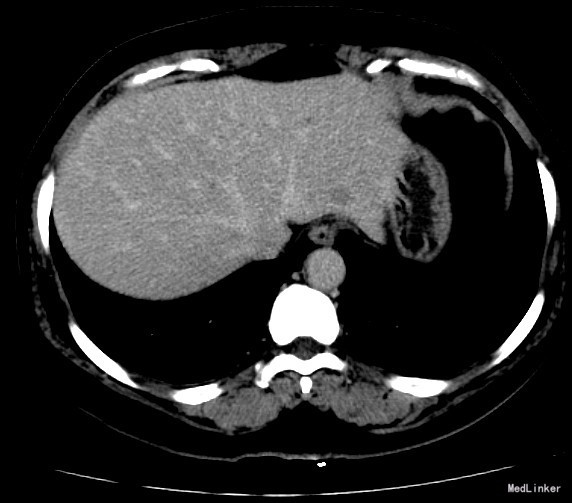

查体:体格检查:体温36.4℃,脉搏72次/分,呼吸18次/分,血压120/70毫米汞柱,神志清,状态可,皮肤及巩膜无黄染,手掌赤痕阳性,红丝赤缕阴性,心肺听诊未闻异常,腹软,无压痛,肝脾肋下未及,移动性浊音阴性,双下肢无浮肿,扑翼样震颤阴性,舌象:舌淡红、苔薄白,脉象:弦脉。 化验:血细胞分析:白细胞计数 6.3 10^9/L、红细胞计数 4.73 10^12/L、血小板计数 175.0 10^9/L、血红蛋白 156 g/L,肝功酶谱:丙氨酸氨基转移酶 22 U/L、碱性磷酸酶 84 U/L、白蛋白 43.8 g/L、总胆红素 13.3 umol/L,甲胎蛋白测定:甲胎蛋白 182.80 ng/mL 彩超:符合慢性肝损伤,肝右叶高回声性质待定0.7cm 肝弹性测定:CAP 252 E 6.9 增强CT:脾大,肝硬化?肝内多发RN,大小约1.2cm,Ⅱ段结节合并Ca变可能性大

诊断:1.乙肝肝硬化 活动性 代偿期 C-P分级 A级 5分 2.肝占位(不除外HCC) 治疗:患者乙肝肝硬化患者,多次于我院中医科住院治疗,本次住院期间中医理疗、抗病毒治疗,查甲胎蛋白增高,并且增强CT发现肝内可疑病灶,考虑原发性肝癌可能性大,于局麻下行TACE治疗,术中诊断为原发性肝癌以微导管超选S2段肝动脉一分支,造影明确为肿瘤供血动脉,注入混悬液(碘化油5毫升+雷替曲塞2毫克)3.2毫升,栓塞微球0.1毫升。

术后患者略乏力,食欲可,二便正常。 查体:神志清,状态可,皮肤及巩膜无黄染,有肝掌,无蜘蛛痣。心肺听诊未闻异常,腹软,无压痛,肝脾肋下未及,移动性浊音阴性,双下肢无浮肿,扑翼样震颤阴性。足背动脉搏动良好。 化验肝功转氨酶略有上升,甲胎蛋白下降。 DSA下肝动脉造影,即是肝癌有效的诊断手段,又是有效的治疗手段,如本例患者,在术中诊断为原发性肝癌的同时,及时进行治疗。TACE创伤小、恢复快、效果较好,是有效的治疗手段